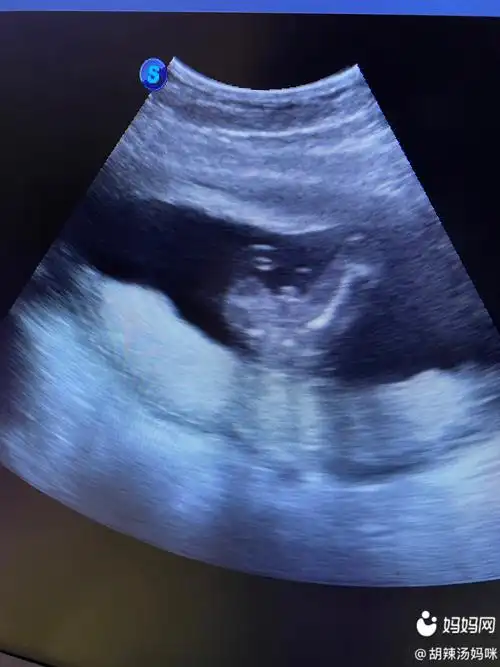

胎儿18周的时候建议您到医院做一次全面的检查,通过b超您可以看到宝宝

怀孕18周胎儿发育图